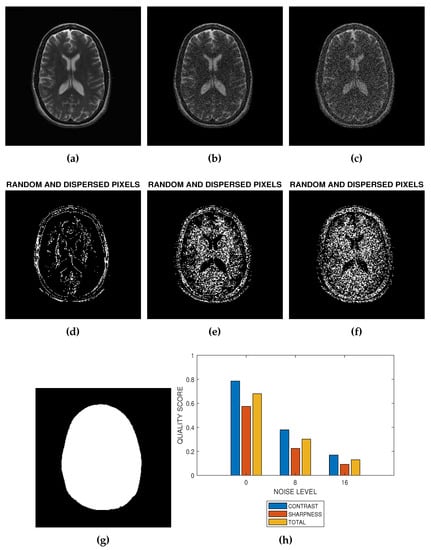

The flowchart in Figure 1 and the images in Figure 2 describe how the proposed method can be implemented. Figure 2 is a slice from a T2 MRI volume data provided by NeuroRx Research Inc. (Montreal, QC, Canada). The four successive steps to implement the algorithm are outlined below.

The implementation of blind noise-based quality assessment in MRI images. (a) The test image provided by NeuroRx Research Inc. (b) Degraded version of the test image in (a) at 8 percent Rician noise. (c) Degraded version of the test image in (a) at 16 percent Rician noise. (d) Random and dispersed pixels in the test image in the absence of noise distortion. (e) Random and dispersed pixels in the test image at 8 percent Rician noise. (f) Random and dispersed pixels in the test image at 16 percent Rician noise. (g) The Foreground extracted from the test image in (a). (h) Variation of contrast, sharpness and total quality scores at Rician noise levels of 0 percent, 8 percent and 16 percent.

- Step 1: Foreground ExtractionForeground extraction is the extraction of the regions of interest in the test image from the background region. Foreground image was extracted using the threshold method. There are three steps to extract the foreground. First is global threshold. The threshold was set at the mean intensity level of the image. The next step is a morphological filling operation followed by area threshold where small regions within the image are eliminated. Knowledge of the foreground shown in Figure 2g allows the determination of the indices of pixels as well as the total number of spatial locations in the foreground region. The number of spatial locations is required in the later implementation steps.

- Step 2: Feature ExtractionThe local Moran feature image is derived by computing the local Moran statistics of the test image according to Equation (1). The spatial weight which define the interaction of pixels is determined by the kernel dimension. In this research, the spatial weight was implemented using a kernel. The local Moran statistics is averaged according to Equation (4) to obtain the global Moran statistics.

- Step 3: Feature ClassificationUsing global threshold, the local Moran feature image is classified into two classes. The first class consist of random and dispersed pixels . The second class consist of clustered pixels:The two classes of pixels are calculated over the foreground region. Figure 2a,b are the images resulting from the addition of 8 percent and 16 percent Rician noise levels to the image in Figure 2a. Random and dispersed feature images corresponding to noise level of 0 percent (Figure 2a), 8 percent (Figure 2b) and 16 percent (Figure 2c) are displayed in Figure 2d–f, respectively.

- Step 4: Quality PredictionQuality prediction is based on two concepts. First, the GMS is considered a perceptual weight which modulates the LMS. Second, the test image is a real grayscale image having heterogeneous features, that is, images in which pixels can be assigned to at least two different classes. In contrast, sharpness and total quality scores shown in Figure 2h are predicted from the perceptually weighted sum of the clustered and dispersed pixels within a grayscale image.The contrast quality score is defined as:The sharpness quality score is defined as:The total quality score is the average of the contrast and sharpness quality scores:Here, we show how the quality scores defined in Equations (7) and (8) can predict the contrast and sharpness quality scores of an ideal, extremely degraded and real MRI slices.